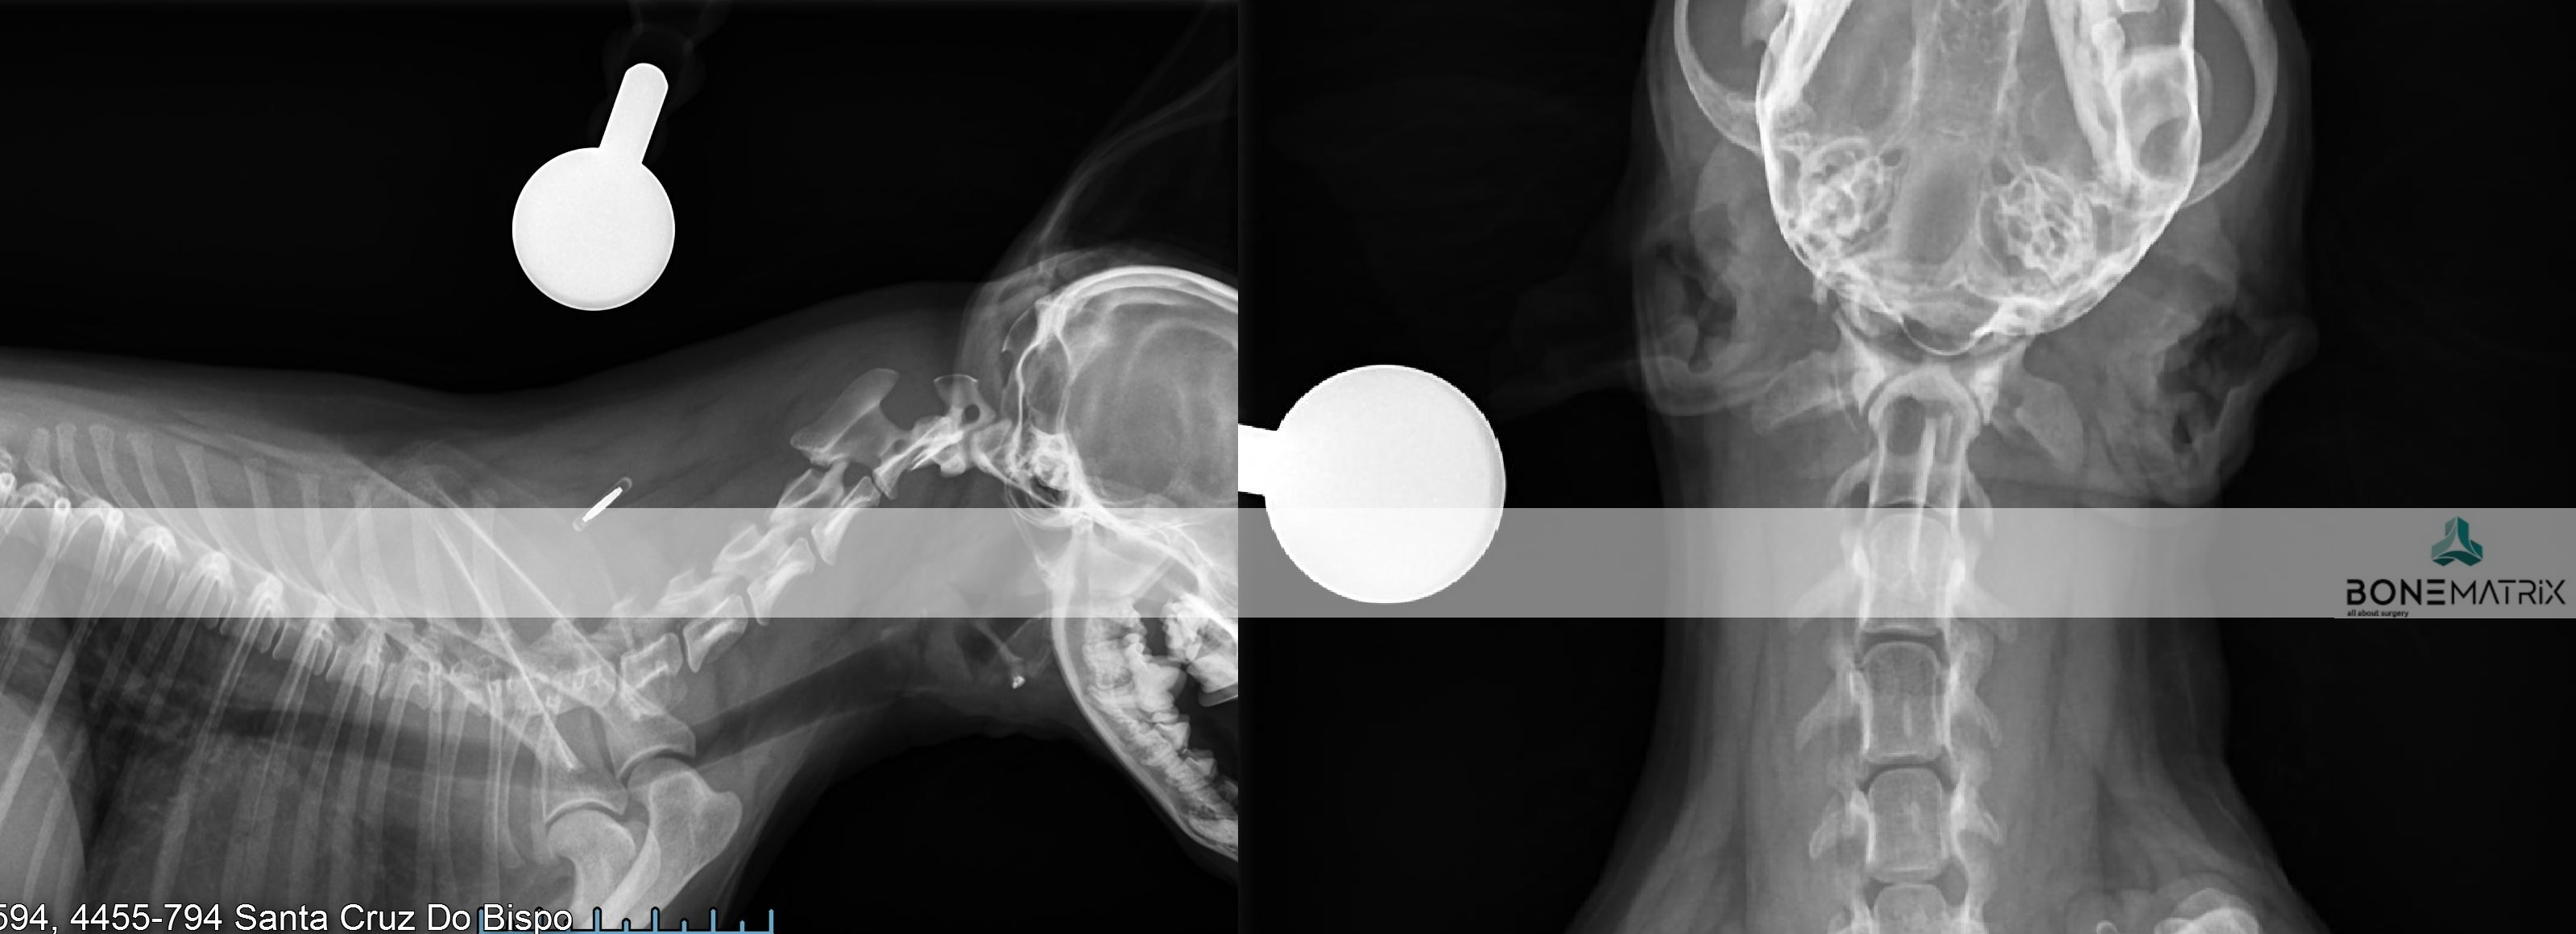

A displasia de anca é uma patologia de desenvolvimento expressa na articulação coxo-femoral (entre o fémur e a pélvis). Esta é a doença ortopédica mais comum nos cães.

O diagnóstico de displasia de anca deve ser realizado idealmente antes dos 5 meses, daí a importância do despiste precoce da doença.

O diagnóstico é feito com recurso a um estudo radiográfico de despiste de displasia de anca (este estudo pode ser realizado a partir dos 4 meses).

Quando a idade do paciente o permite e este se revela um bom candidato, pode em idade imatura, ser realizada uma DPO (double pelvic osteotomy), sendo este um procedimento preventivo do desenvolvimento de displasia de anca.

Quando o animal é adulto a única opção de tratamento curativa passa pela prótese total de anca (THR). Esta permite substituir a articulação afetada na sua totalidade e devolver a qualidade de vida ao paciente até ao fim da vida dele.